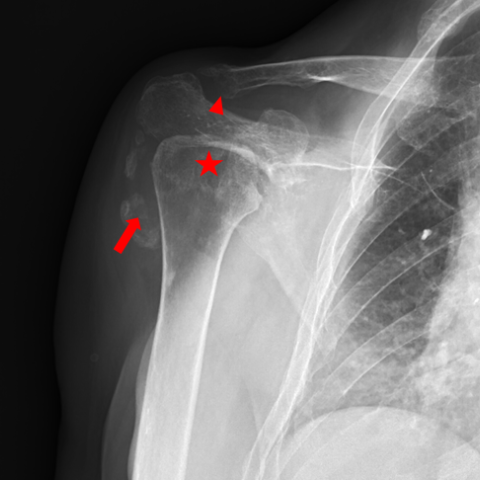

1623864b0e61ea9de14ecb324ed06575.png

本次右肩前后位 X 光显示肱骨头的破坏、畸形和半脱位(*)、锁骨外侧端骨溶解(→)以及关节内钙化(长→)。